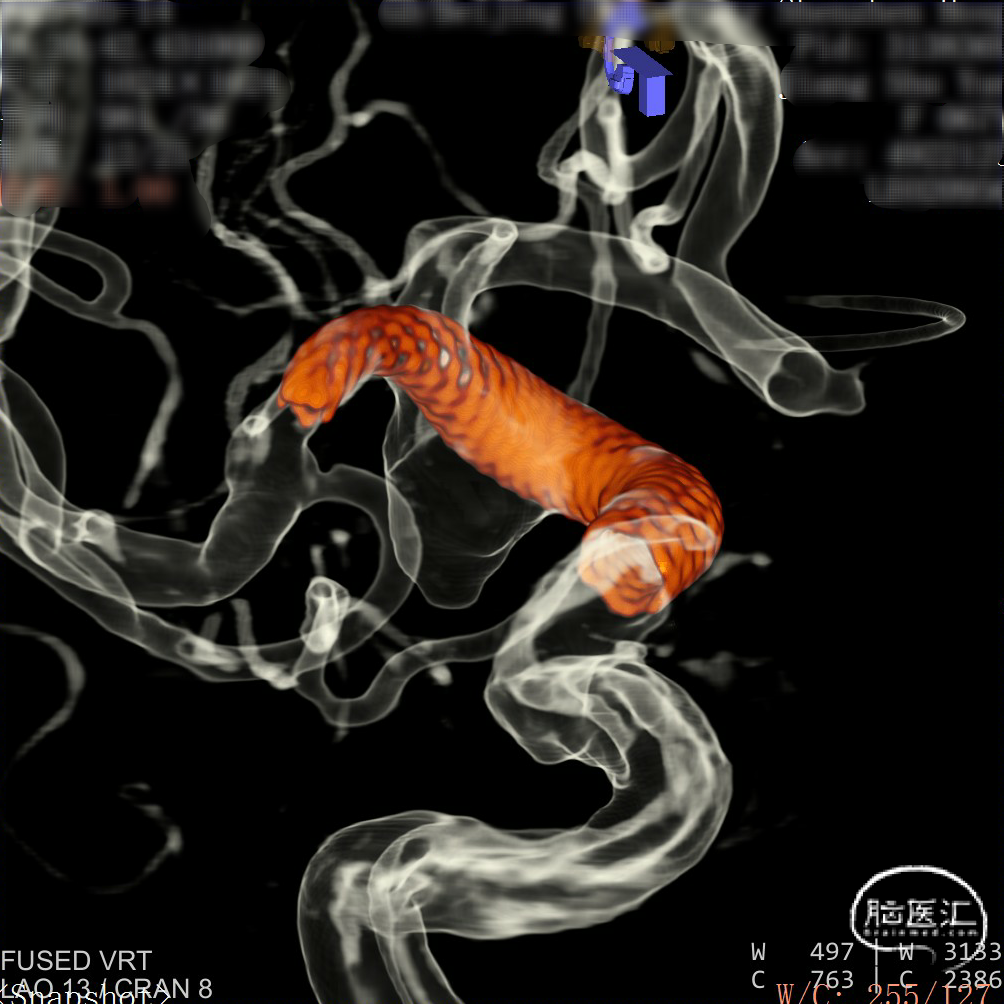

CTA:右侧颈内动脉C7段动脉瘤。

老年女性患者,检查发现右侧颈内动脉C7段大动脉瘤,动脉瘤直径大于10mm,形态不规则,宽颈,手术指征明确,既往高血压、肿瘤病史,首选微创介入手术,术中造影证实动脉瘤直径大于10mm,绝对宽颈,形态不规则,局部仔瘤改变,右侧脉络膜前动脉从瘤体发出;微创介入血流导向装置是较优选择。

DSA造影:

工作角度:

大动脉瘤的微创介入栓塞治疗存在需要支架辅助,瘤颈处理困难、复发率高、费用高等难点;血流导向密网支架置入是较优选择,操作相对简单,不用填塞弹簧圈,完整覆盖瘤颈,远期明显降低再复发概率。本病例为右侧颈内动脉C7段累及脉络膜前动脉的大动脉瘤,该部位解剖结构复杂,周围血管分支多,在操作过程中要避免损伤正常血管,否则会引发严重脑缺血事件;其次,动脉瘤与脉络膜前动脉关系密切,既要处理好动脉瘤,又要保证脉络膜前动脉的血供不受影响,这对手术操作精度要求较高;再者,瘤颈的处理较为棘手,瘤颈较宽,传统弹簧圈栓塞难以达到理想效果,且容易复发。血流导向密网支架置入可解决这些问题,术前需借助3D-DSA,全面评估动脉瘤大小、形态、瘤颈宽度、与周围血管关系,制定精准手术方案。操作时,微导管的到位是关键一步,要在路径图引导下,小心、轻柔操作,避免刺激血管引发痉挛或动脉瘤破裂。释放支架过程中,要注意关注支架位置和贴壁情况。释放后要通过多角度造影,确认支架完全覆盖瘤颈,且支架内血流通畅,分支血管未受影响。同时,术后要密切观察患者神经功能变化,预防血栓形成、血管痉挛等并发症,及时给予抗血小板、解痉等药物治疗。